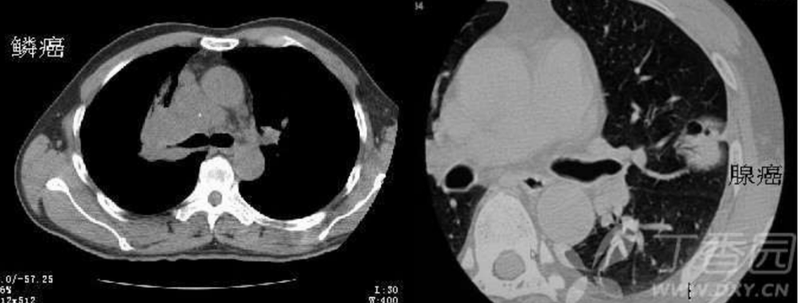

支气管充气征分型与病变的联系

大叶性肺炎、肺水肿等急性渗出性病变其病理变化主要在肺泡,并不侵犯支气管,同时,急性渗出性病变病程相对较短,以渗出为主,此时肺实质的变化对支气管的影响较小,基本不足以引起其病变范围内支气管的形态和走行的改变,因此,其支气管充气征的表现为管腔未见明显改变,管壁光整,分支完整,走行柔软自然,即I型青枝型。I型青枝型所显示的支气管管腔未见明显改变,走行自然,整个支气管树柔软状如青树支,名为青枝型,这是肺炎C征象;Ⅱ型,所显示的充气支气管管腔以扩张为主,名为扩张型;Ⅲ型,显示支气管管腔狭窄与扩张并存,小分枝残缺而使支气管树形态不完整,支气管走行僵直,状如枯枝,命名为枯枝型;Ⅳ型,支气管充气征与支气管黏液征并存,名为复合型。

I型空气支气管造影征:

在大片肺实变病灶内的细条状空气密度影,或直径1mm的小泡状空气密度影,连续的几个层面都能出现,其支气管壁柔软,无僵硬感,分支自然,支气管径由粗变细;这是肺炎C征象。

Ⅲ型支气管造影征(枯树枝征):

在肺大片实变阴影中,有较大的充气支气管影像,而较小的支气管不显影,支气管管壁不规整,凹凸不平,广泛性狭窄、僵硬、扭曲。该征和肺炎中的充气支气管不同的是小支气管不显影,充气的大支气管管壁不规整,凹凸不平,广泛性狭窄、僵硬、扭曲,走形不自然。该征象是肺泡癌的特征性表现,无论从发病机制和影像表现都和肺炎的充气支气管征有本质的区别。